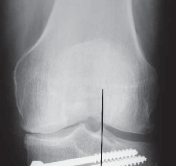

16. Intraoperative complications

1. Fracture of the medial or lateral cortex (

FIG 4A

)

2. Intra-articular extension of the osteotomy (

FIG 4B

3. Intra-articular screw placement

18. Delayed postoperative

1. Patella baja

2. Nonunion or delayed union

3. Hardware failure (

FIG 4C

4. Collapse with loss of osteotomy correction (

FIG 4D–F

### FIG 4 • A. Lateral cortical breach stabilized with a three-hole 1/3 tubular plate. This was placed after the osteotomy had propagated through the lateral wall of the tibia. B. Intra-articular extension of the osteotomy that was not repaired intraoperatively, with subsequent osteotomy collapse and hardware breakage. C. Hardware failure. There is no collapse of the osteotomy, but the distal screws failed secondary to micromotion.

### FIG 4 •

(continued)

D–F. Collapse of the osteotomy with loss of correction. D. One-week postoperative image with mechanical axis at lateral tibial spine. E. Four-month postoperative image with significant osteotomy collapse (4 degrees of varus). F. Ten-month postoperative image with final osteotomy collapse into 10 degrees of varus. The patient started off with a 15-degree varus deformity.**